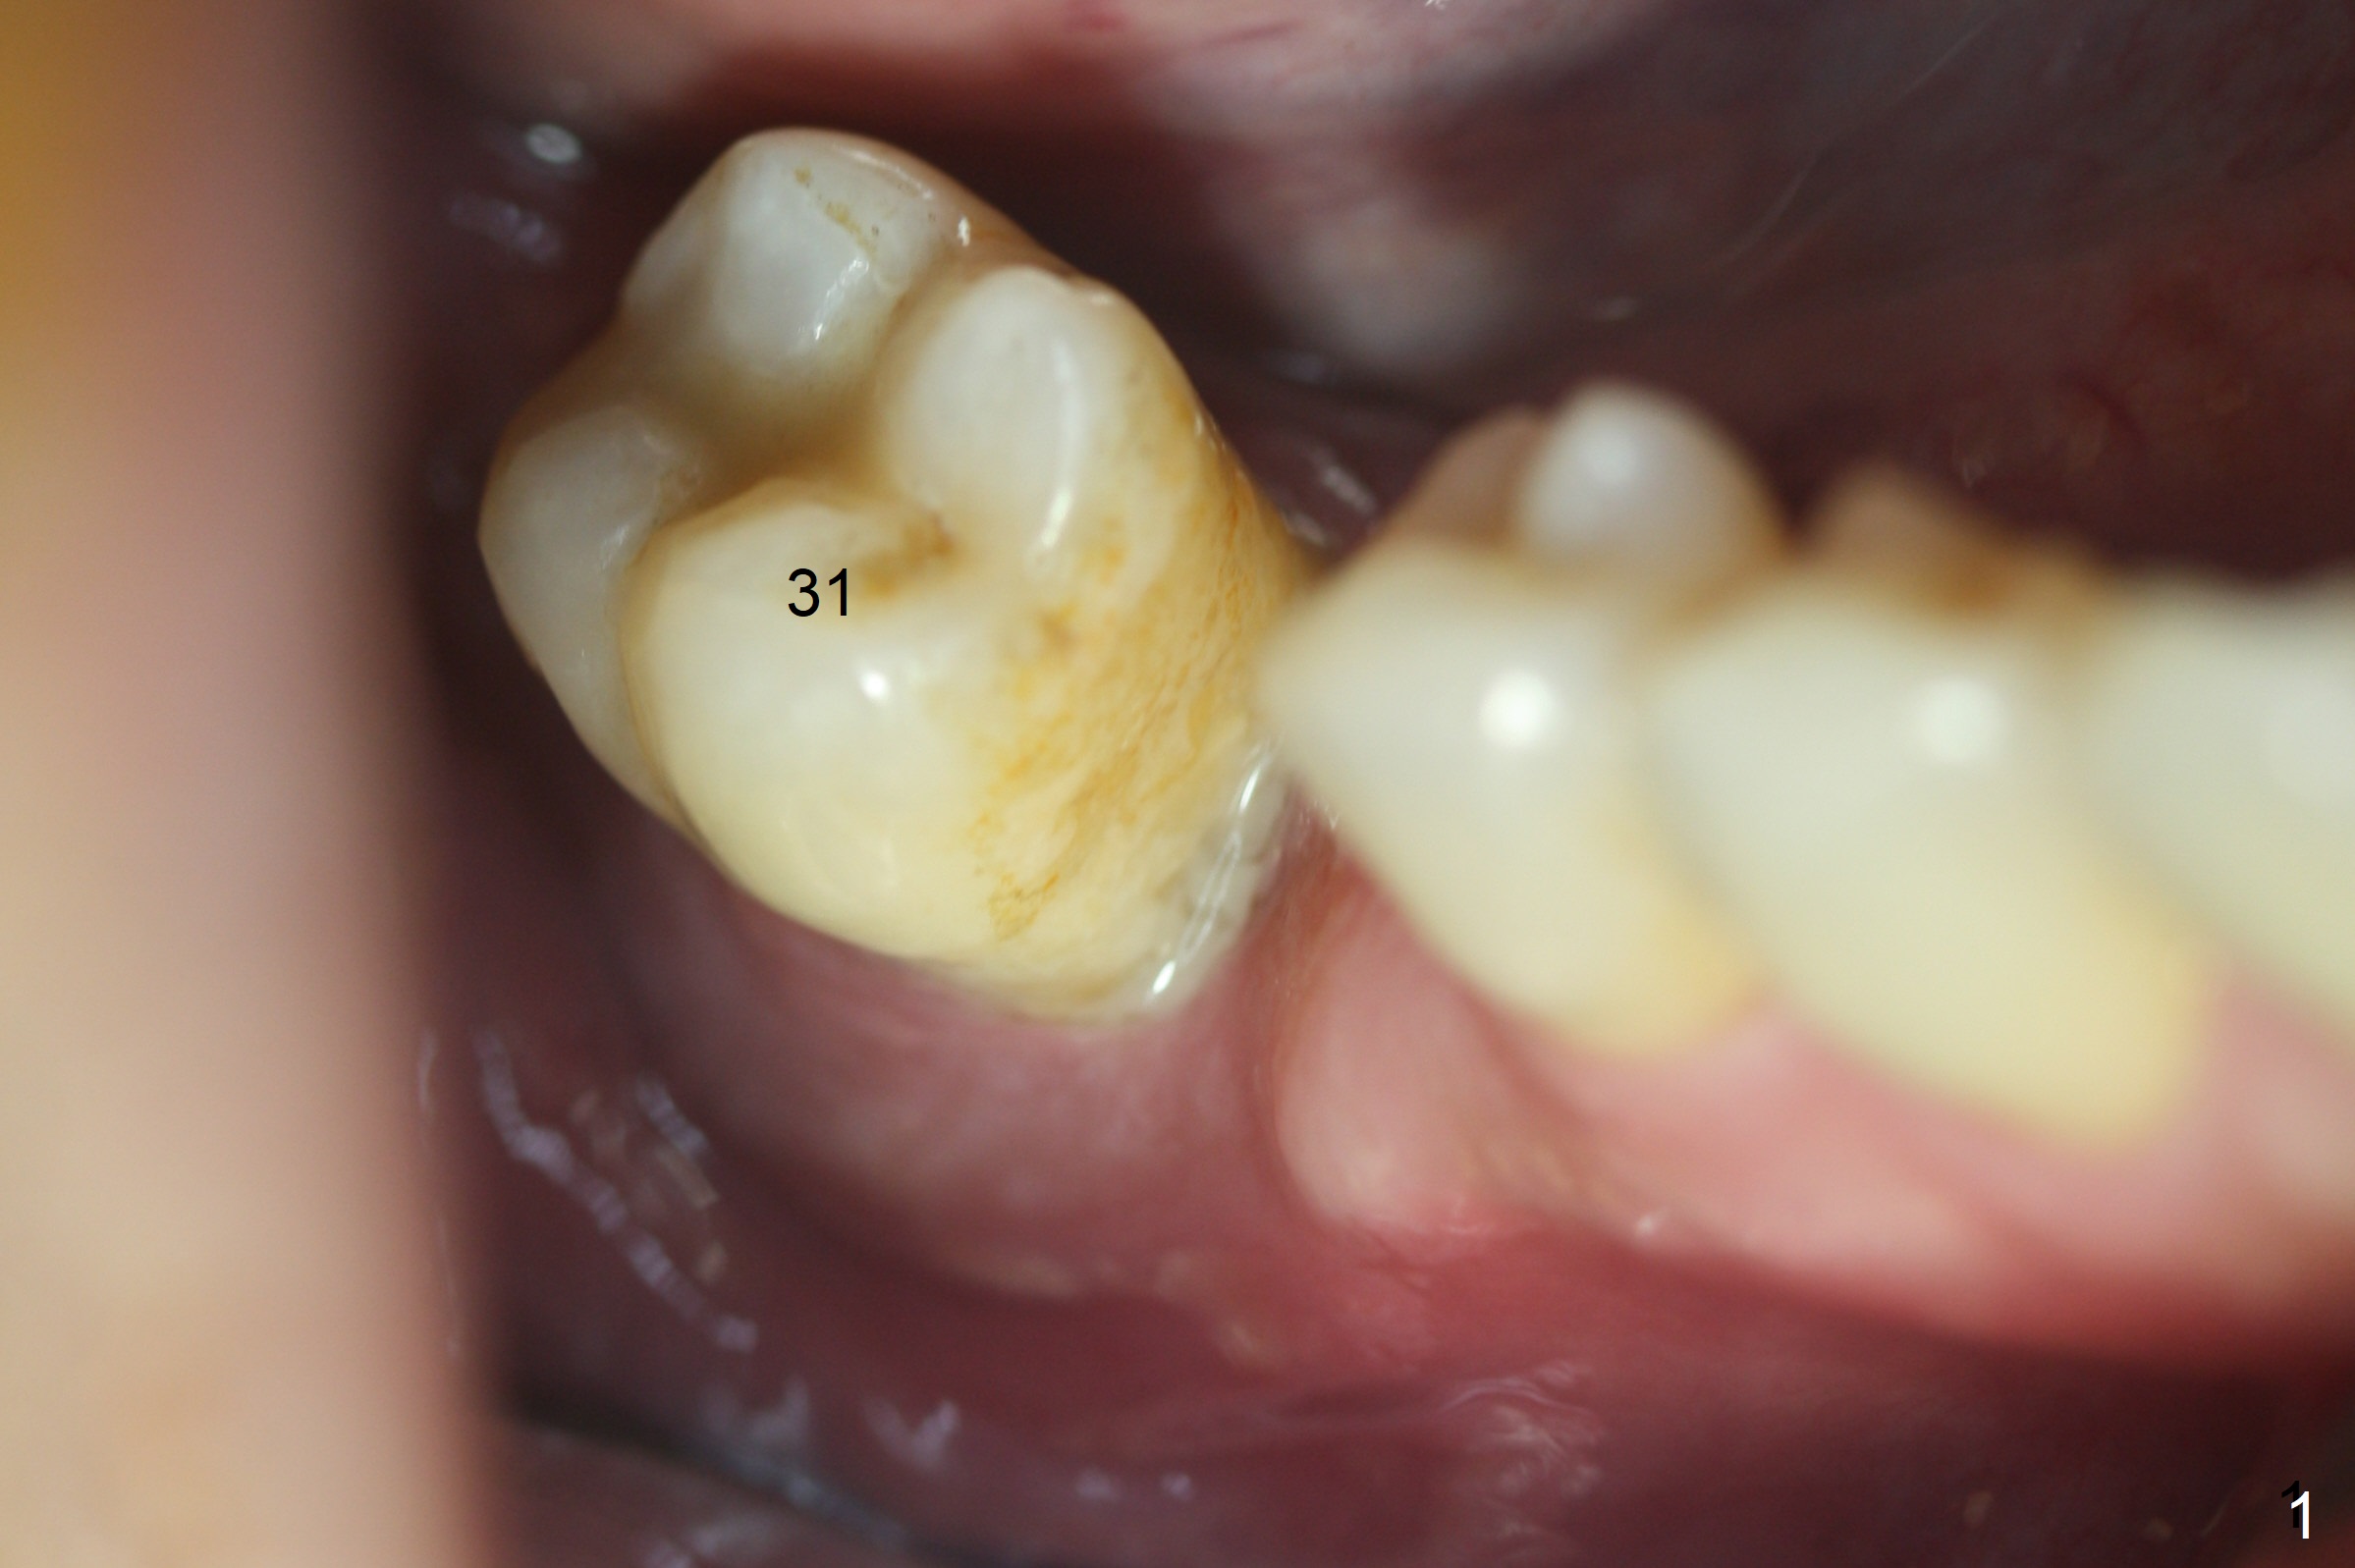

Extraction of the mobile tooth #31 (Fig.1) and debridement of the large socket are not difficult. But making osteotomy buccally does not seem to be easy. It will be difficult to restore. Instead, socket preservation is accomplished by filling the socket with approximately 1.5 cc of Mineralized Cortical/Cancellous allograft until the crest (Fig.2,5). The socket opening is closed by insertion of 4 pieces of PRF membranes (Fig.3) and 4-0 Chromic gut sutures (Fig.4). In the end of surgery, it appears that osteotomy in the center of the socket could be a better approach. Postop re-analysis of CT (Fig.6) and PA (Fig.7) shows that there is 3.9 mm of the native bone to support a 5.5x10 mm implant. Sinus Lift Master Kit should be used with 2 mm initial drill and 2.8 and 3.6 mm round drills with 4 mm stopper.